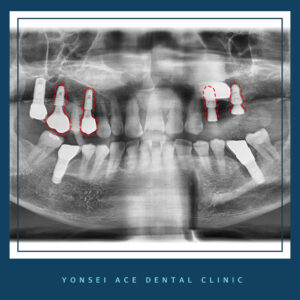

우선 기존 임플란트 픽스쳐 제거 수술을 진행하였습니다.

임플란트를 제거한 자리에는 염증을

깨끗하게 제거하고 뼈이식과 함께

임플란트를 재식립하였는데요.

수술 후 사진을 보시면 염증이 발생한 오른쪽 부위도

치조골이식술로 인해 잇몸뼈가 튼튼하게 다져졌고,

보철물을 씌울 예정입니다.

이외에도 문제가 있었던 오른쪽 상악 부분에

임플란트 식립을 진행하였고 해당 부위는

보철물까지 마무리되었는데요.